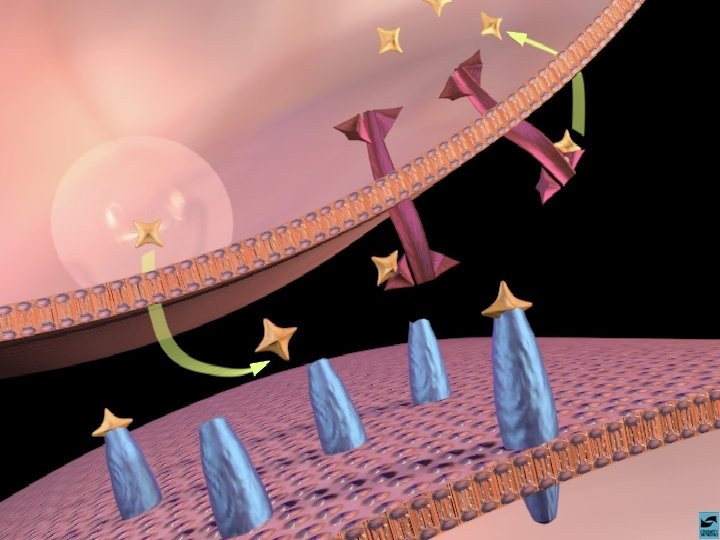

A AÇÃO DAS DROGAS NO SISTEMA NERVOSO CENTRAL A SINAPSE

A AÇÃO DAS DROGAS NO SISTEMA NERVOSO CENTRAL OS NEUROTRANSMISSORES - NORADRENALINA - SEROTONINA - DOPAMINA - GABA - ACETILCOLINA

ANFETAMINAS E COCAÍNA EFEITOS CEREBRAIS: ATIVA OS SISTEMAS DOPAMINÉRGOS MESOLÍMBICOS E MESOCORTICAIS, INIBINDO A RECAPTAÇÃO DE DOPAMINA NOS TERMINAIS SINÁPTICOS E PROMOVENDO SUA LIBERAÇÃO NAS SINAPSES.